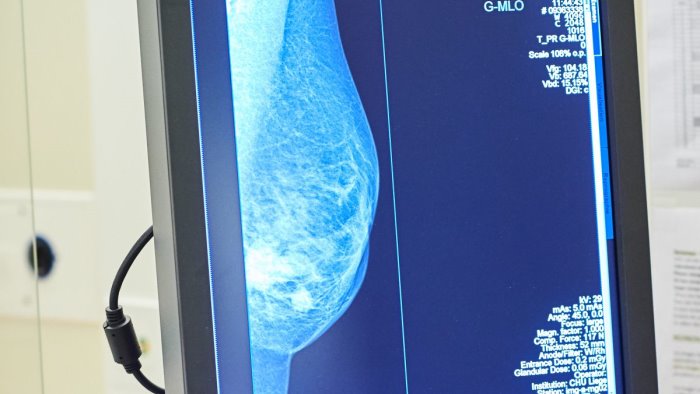

A quasi tre mesi dall'istituzione dell'apposito fondo nazionale di 20 milioni di euro, i test genomici per il carcinoma mammario non sono ancora disponibili gratuitamente in tutta Italia. "Per migliorare la qualità di vita delle pazienti e permettere risparmi di preziose risorse pubbliche bisogna accelerare le procedure affinchè questi esami siano disponibili senza alcuna spesa. Per questo chiediamo un intervento diretto e immediato del Ministero della Salute affinchè approvi al più presto il decreto attuativo". E' questo l'appello che sostiene Europa Donna Italia, il movimento per la tutela dei diritti delle donne con tumore al seno che a inizio 2021 ha avviato la campagna nazionale "Chemio: Se Posso la Evito". I principali risultati dell'iniziativa sono stati presentati oggi in una conferenza stampa virtuale. In poco più di due mesi sono state raccolte oltre 15.000 firme ad una petizione on line. Sono poi stati raggiunti oltre 564mila utenti del web attraverso un'intensa attività sui principali social media.

"Abbiamo ottenuto buoni risultati e un ottimo sostegno da parte di pazienti, caregiver, clinici e semplici cittadini - afferma Rosanna D'Antona, presidente di Europa Donna Italia -. Si tratta di una chiara testimonianza che conferma quanto sia sentita la necessità della personalizzazione delle cure, soprattutto in questo momento difficile caratterizzato dal Covid-19. Europa Donna Italia si è battuta perchè non solo in Lombardia, Toscana e Provincia Autonoma di Bolzano - dove i test sono finanziati da fondi regionali - ma in tutta la Penisola si possa evitare la somministrazione di chemioterapie inutili. Sono circa 8.000 le pazienti che, ogni anno, ricevono queste cure anche se non ne hanno necessità. Ringraziamo il Governo e il Parlamento per quanto fatto finora. Bisogna però al più presto emanare il provvedimento che renda effettivamente utilizzabili i test genomici senza costi per le donne".

"Questi esami rappresentano una fonte di risparmio importante per i conti pubblici - aggiunge il professore Carlo Tondini, direttore Oncologia Medica dell'Ospedale Papa Giovanni XXIII di Bergamo -. Nello studio BONDX, condotto in Regione Lombardia su 400 pazienti, abbiamo provato a quantificare da un punto di vista economico i vantaggi ottenuti. La ricerca ha evidenziato come l'uso di due test, da 2.000 euro ciascuno, abbia evitato una chemioterapia dal costo di 7.000 euro. Il risparmio diretto sulla spesa farmaceutica regionale ammonta a circa 3.000 euro per paziente a cui vanno aggiunti i costi indiretti per malati e caregiver. Abbiamo, inoltre, evitato ad una donna di essere sottoposta ad una chemioterapia, dopo l'intervento chirurgico, e preservato così la sua qualità di vita evitando effetti collaterali".